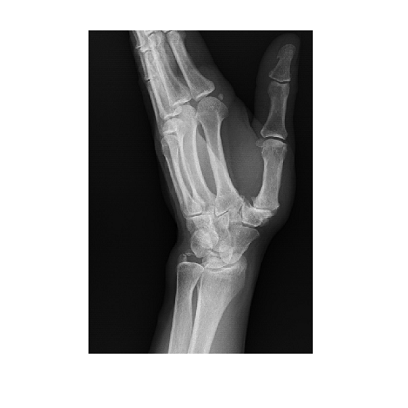

Na czym polega zabieg

Zabieg endoplastyki polega na zastąpieniu uszkodzonego stawu endoprotezą, co pozwala na:

- skuteczne złagodzenie dolegliwości bólowych,

- przywrócenie prawidłowej ruchomości kciuka,

- poprawę funkcjonalności ręki.

Dzięki zastosowaniu nowoczesnych technik operacyjnych i wysokiej jakości implantów, pełna ruchomość ręki jest możliwa do osiągnięcia już po około 6 tygodniach od zabiegu.